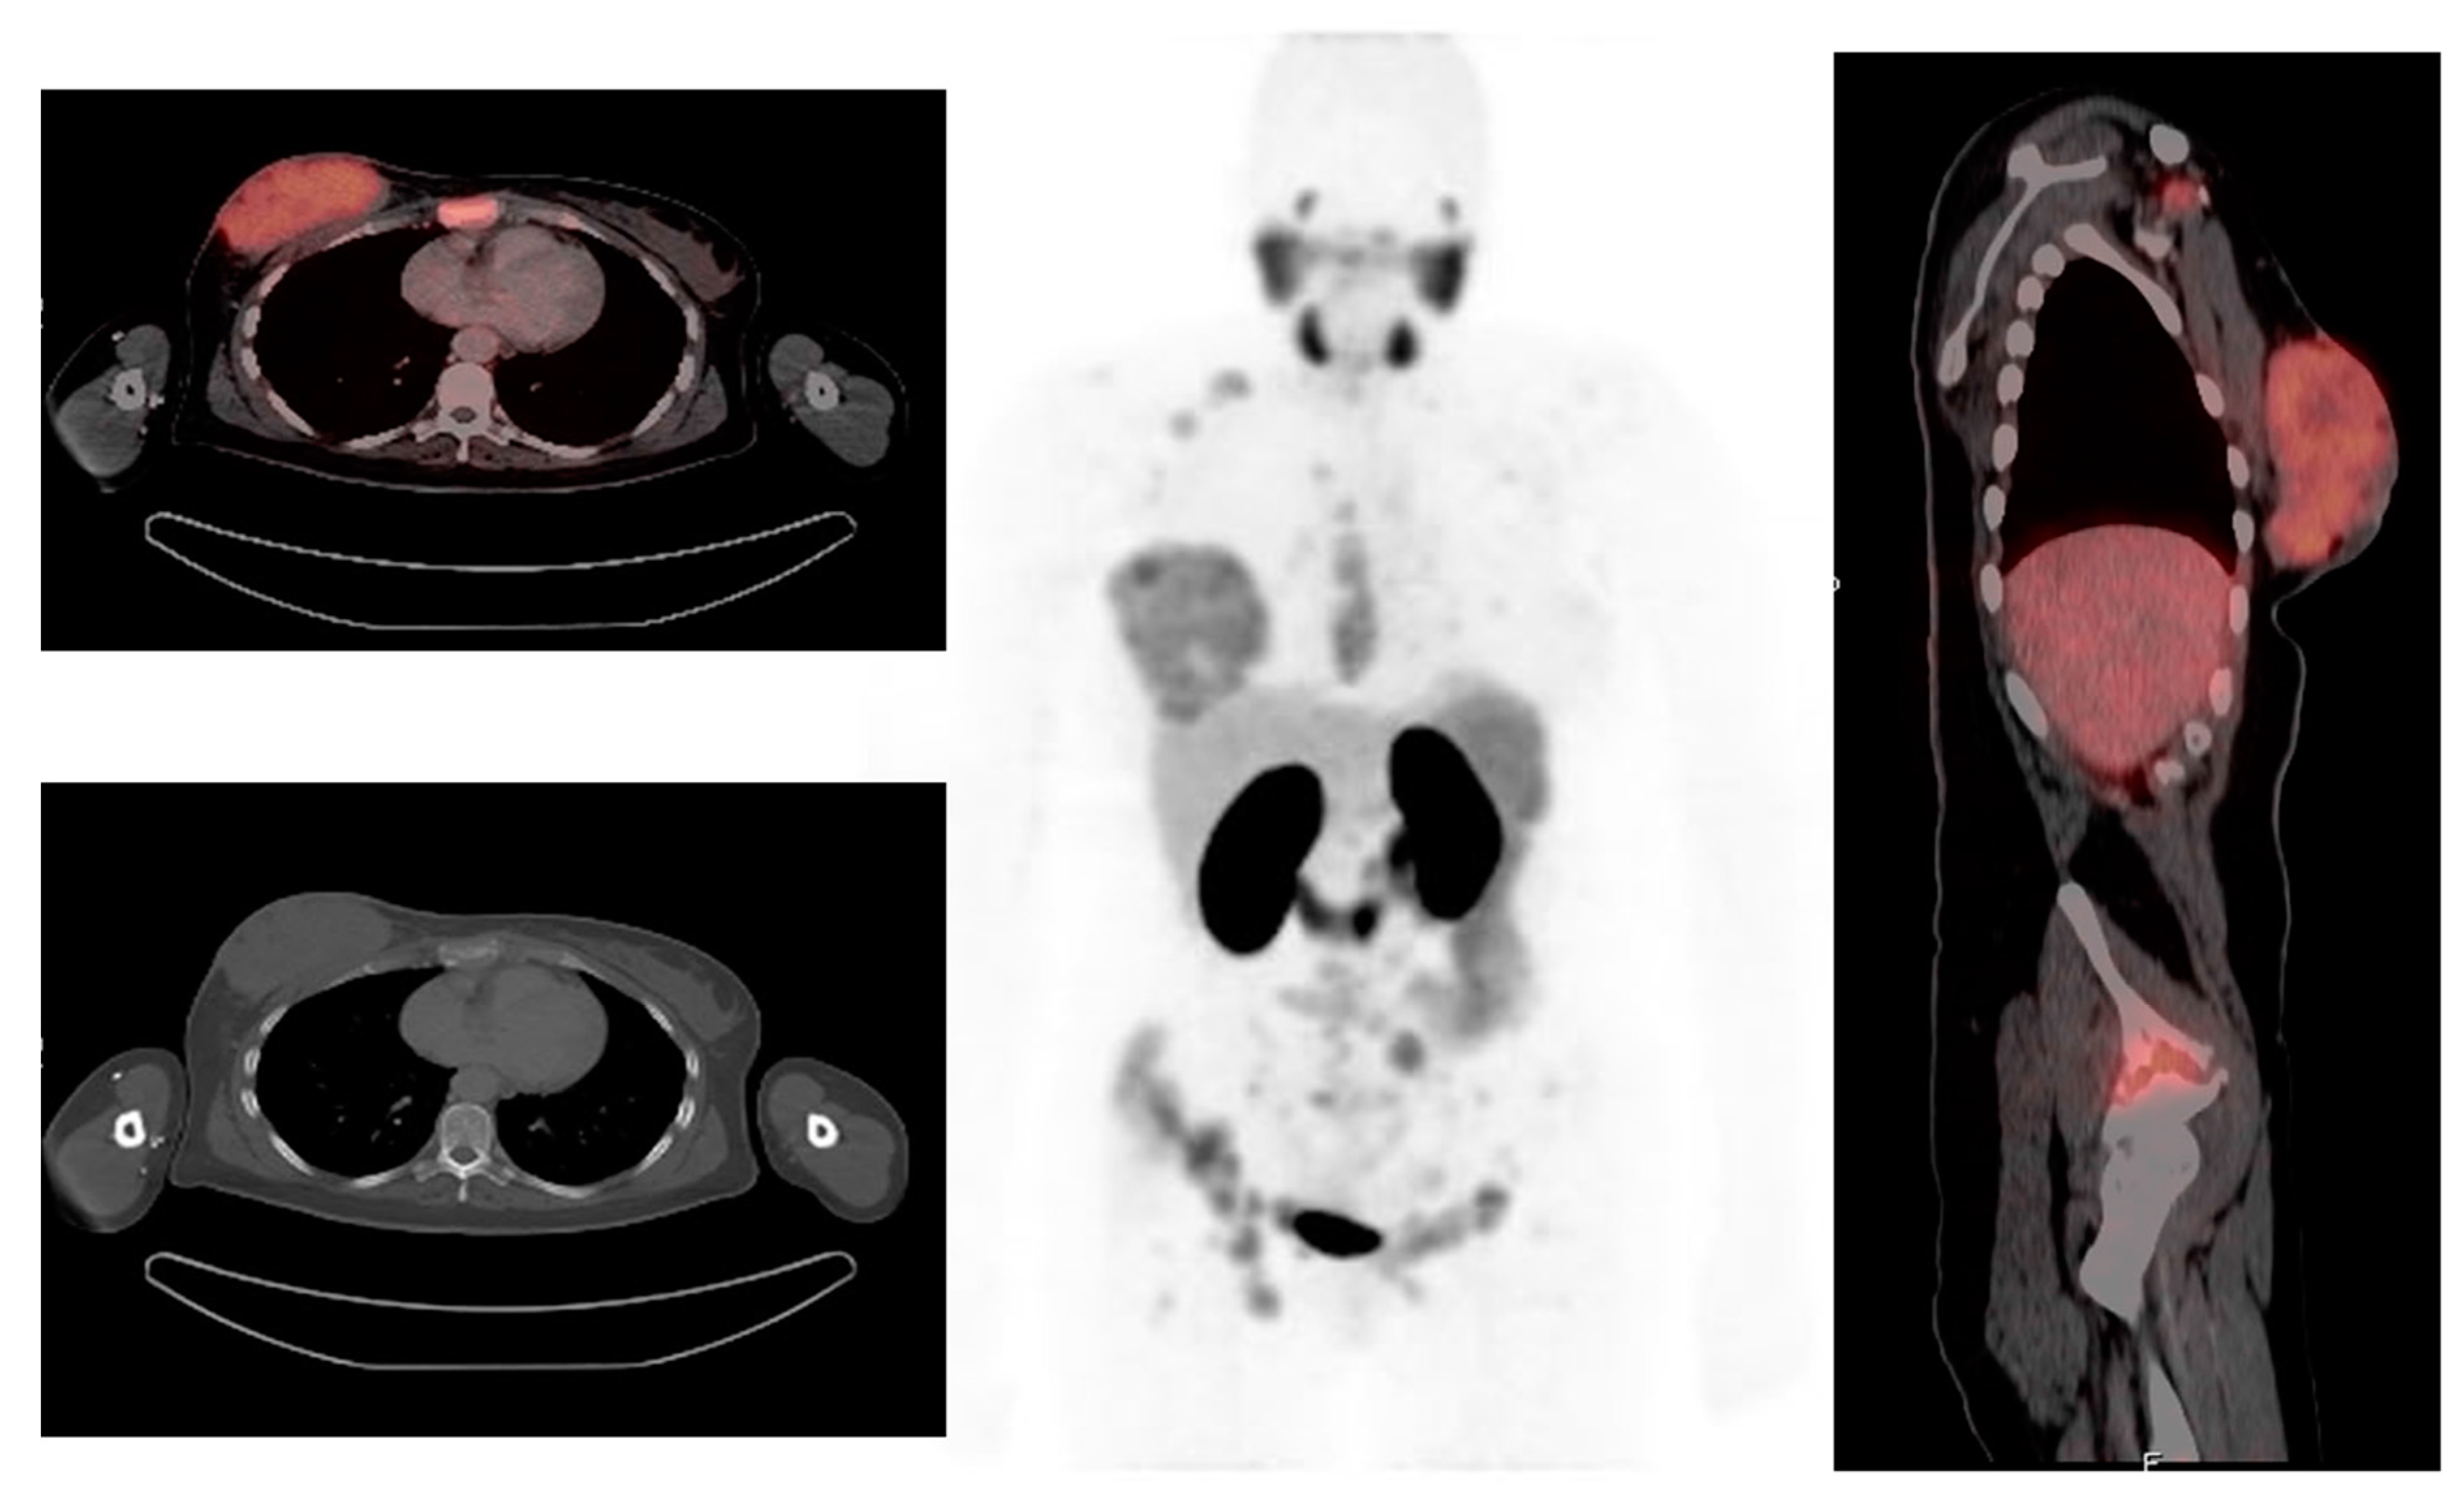

- Komek, H.; Can, C.; Guzel, Y.; Oruc, Z.; Gundogan, C.; Yildirim, O.A.; Kaplan, I.; Erdur, E.; Yildirim, M.S.; Cakabay, B. (68)Ga-FAPI-04 PET/CT, a new step in breast cancer imaging: A comparative pilot study with the (18)F-FDG PET/CT. Ann. Nucl. Med. 2021, 35, 744–752. [Google Scholar] [CrossRef]

- Elboga, U.; Sahin, E.; Kus, T.; Cayirli, Y.; Aktas, G.; Uzun, E.; Cinkir, H.; Teker, F.; Sever, O.; Alper, A.; et al. Superiority of 68Ga-FAPI PET/CT scan in detecting additional lesions compared to 18FDG PET/CT scan in breast cancer. Ann. Nucl. Med. 2021, 35, 1321–1331. [Google Scholar] [CrossRef]